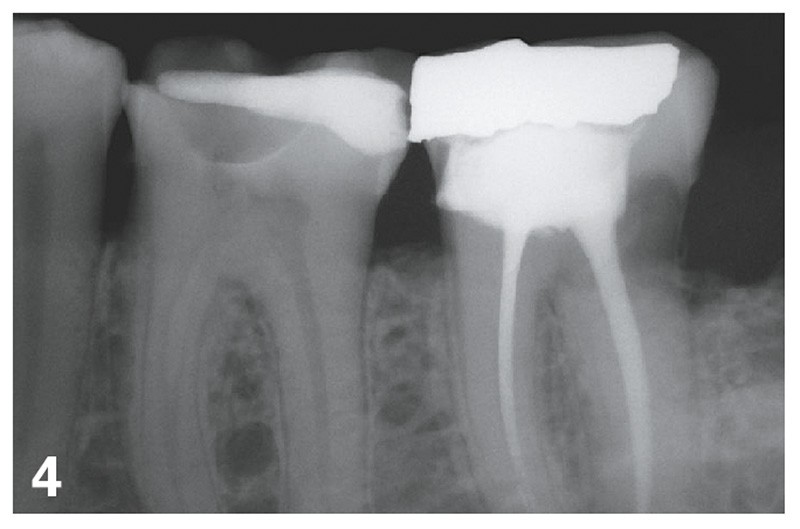

Dans le cas illustré par les figures 1 à 4 ci-dessus, les 16, 17 et 36 doivent être soignées et restaurées. Le choix des onlays permet :

– une solution économe en tissus dentaires ;

– une liberté d’honoraires ;

Le choix de trois couronnes périphériques aurait nécessité de présenter au moins une alternative en RAC-0, en l’occurrence des couronnes métalliques. Bien entendu, de nombreux patients auraient refusé et auraient choisi une option plus esthétique. Les honoraires auraient cependant été plafonnés pour cette option RAC-0.